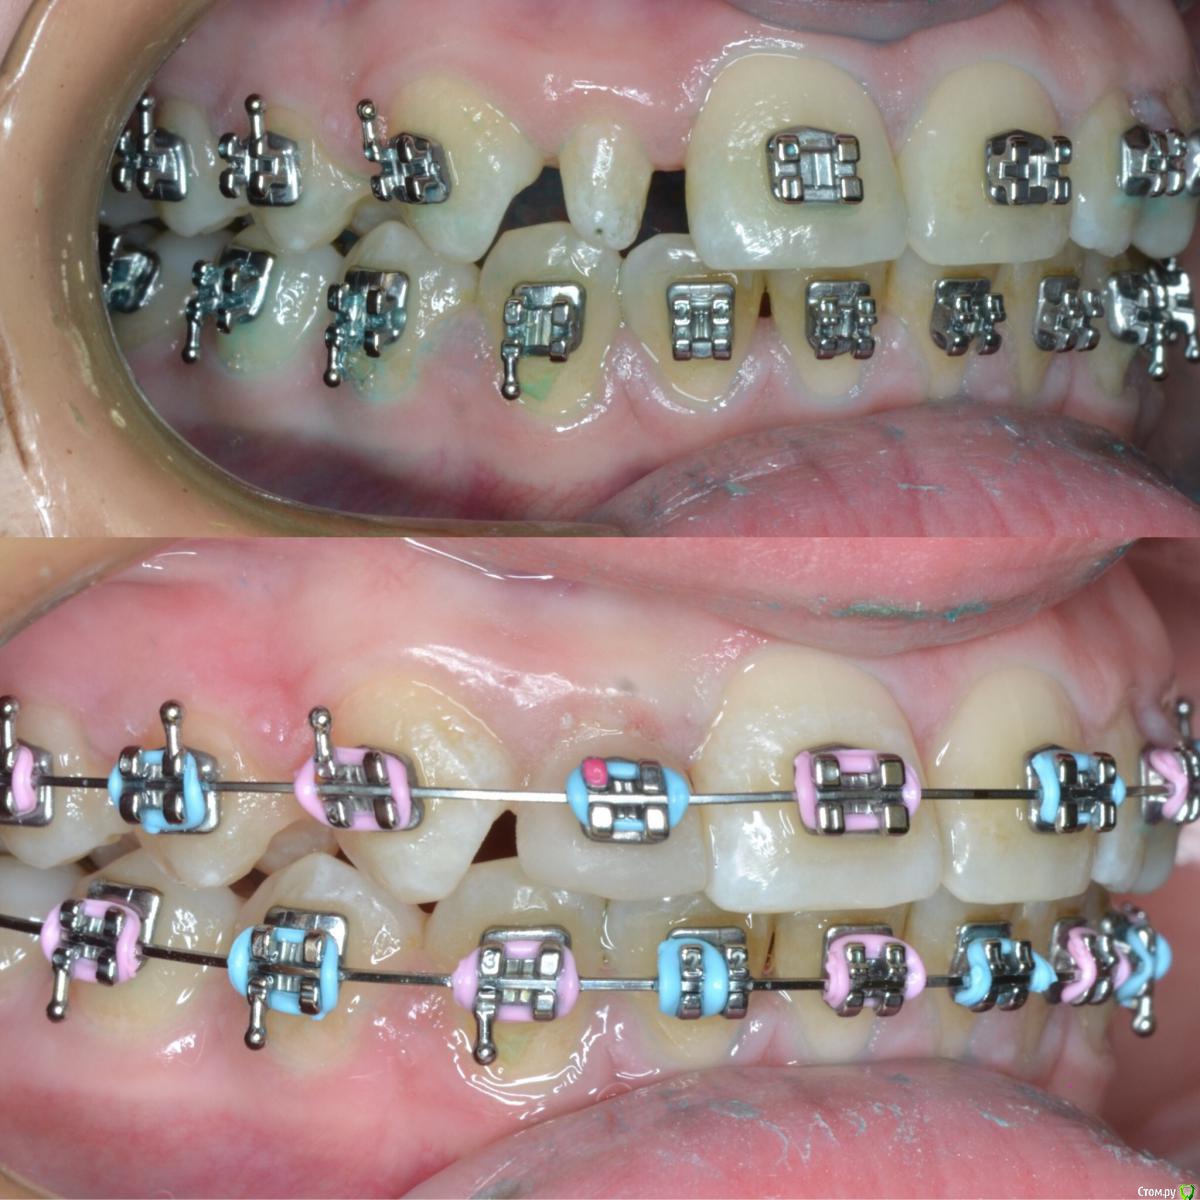

CRAZYDUCK Опубликовано 20 мая, 2018 Автор Поделиться Опубликовано 20 мая, 2018 Шиповидный боковой резец 1.2 . Изначально был дефицит места . Место создали -зуб восстановили ( реставрация временная - на время ортодонтического лечения , после полноценная реставрация). 1 Ссылка на комментарий